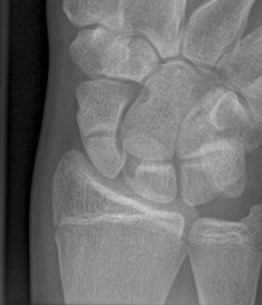

Nonunion with minimal displacement and minimal resorption

Nonunion with significant displacement and bone resorption

Proximal pole fracture with displacement and absorption